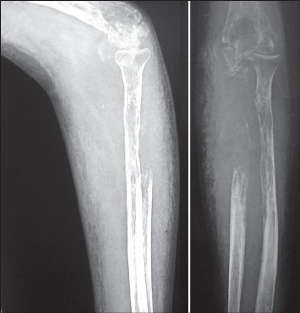

Диагностика болезни Горхема обычно включает рентгенографию, магнитно-резонансную томографию (МРТ) и биопсию костной ткани. Эти методы помогают выявить изменения в костной структуре и исключить другие заболевания, которые могут вызывать подобные симптомы.